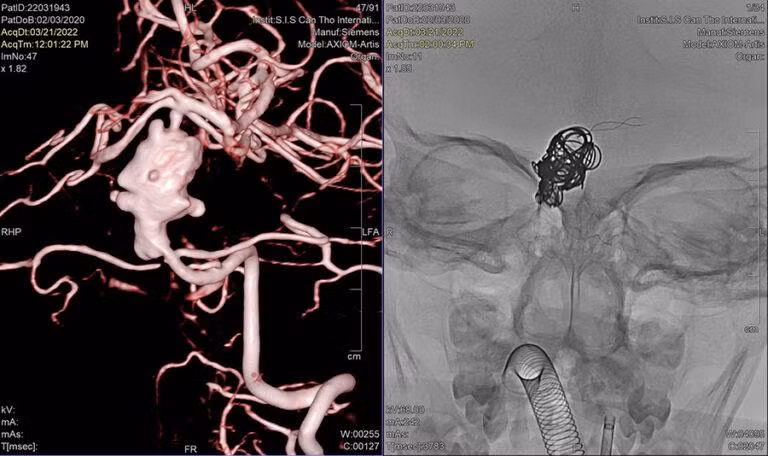

Bệnh nhi được chỉ định chụp mạch máu não bằng máy MRI 3 Tesla. Kết quả cho thấy có khối túi phình hình dáng phức tạp, nằm ở vị trí động mạch thân nền, nơi có vùng não điều khiển nhiều chức năng quan trọng của cơ thể.

Túi phình mạch máu não khổng lồ ở vị trí hiểm hóc được bít lại, tránh cho bé gái nguy cơ bị vỡ túi phình, đột quỵ xuất huyết não. Nguồn: BV .

Vấn đề khó nhất trong trường hợp bé A.N. là túi phình hình thoi dài hơn 30mm, kéo hết cả động mạch thân nền, không có cổ, không có cuống làm cho việc điều trị nút mạch vô cùng khó khăn.